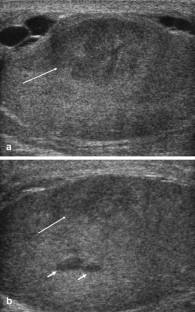

Fig. 2